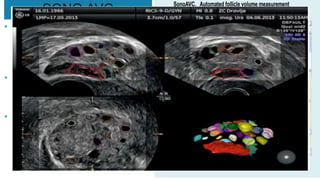

SONO AVC

• SONO AVC is a 3D software with

automated calculation the no. of

follicles in individual ovaries and

gives good count assessment.

• Very useful for antral follicle

count assessment in IVF

protocols.

• For diagnosis of PCOS and early

prediction of ovarian

hyperstimulation when 3D

doppler is employed alongside

VOCAL

• VOCAL(virtual organ comp aided analysis) is an inbuilt

software in an advanced 3 D machine

which helps in measuring volume and

vascularity of any structure e.g ovary,

endometrium etc.

• Used by infertility specialist to assess

ovarian volume, stromal and

endometrial volume under infertility

protocol &PCOS

• In case of PMB, to evaluate

endometrial volume and chances of

malignancy (under research)